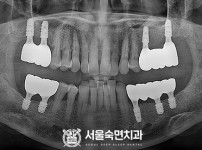

임플란트-전후사진2